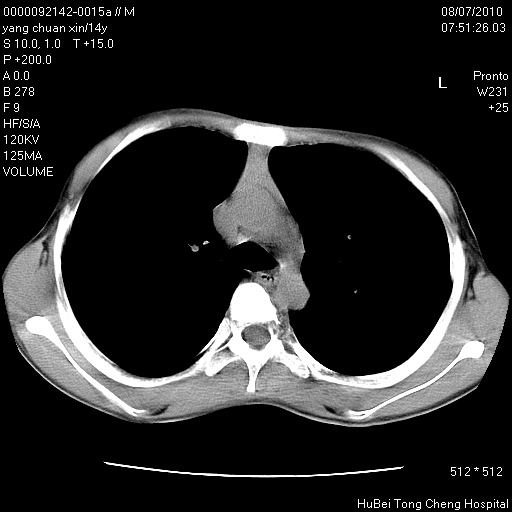

患者 女,36岁。右侧腰腿痛半月余。腰骶椎mr平扫偶然发现骶椎异常信号。

临床诊断:1)腰椎间盘突出症。2)骶椎肿瘤性病变?

骶椎ct平扫(层厚、层距均为5mm),图像如下: